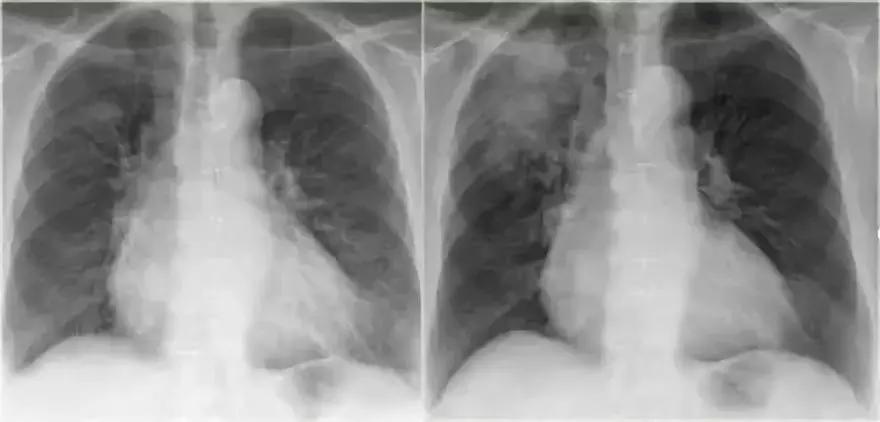

(1)影像一

图3 典型大叶实变

影像学表现:

➢ 左下肺边界模糊的密度增加的阴影

➢ 依然可见心脏轮廓,阴影出现在下叶

➢ 空气-支气管征

➢大叶性实变始于外周,由肺泡孔氏孔扩散

➢边界实变,由于一些肺泡参与实变,一些肺泡没有涉及,造成边缘模糊➢当病变发展到叶间裂,形成尖锐的轮廓,实变不能越过叶间裂

➢支气管周围肺泡更加密集,所以支气管相对更加明显可见,形成空气-支气管征(箭头所示)

➢肺实变时,肺体积应该没有或仅有轻微缩减。与肺不张有明显的不同

➢一般实变不会引起肺体积增大,但可见于克雷伯杆菌,时见于肺炎链球菌、TB和肺癌伴阻塞性肺炎

2.病例二

➢ 胸部X线显示,肺右上叶出现密度增加的模糊阴影,肺体积没有缩小

➢ 右肺门在正常的位置

➢ 箭头所示为空气-支气管征

➢ 结合适当的临床诊断,很像大叶或肺段性肺炎

➢ 然而,如果患者出现体重减轻,或症状时间持续较长,可能存在慢性实变的病因。

➢ 诊断结果为,肺炎链球菌引起的急性大叶性肺炎

图4 肺炎链球菌引起的急性大叶性肺炎